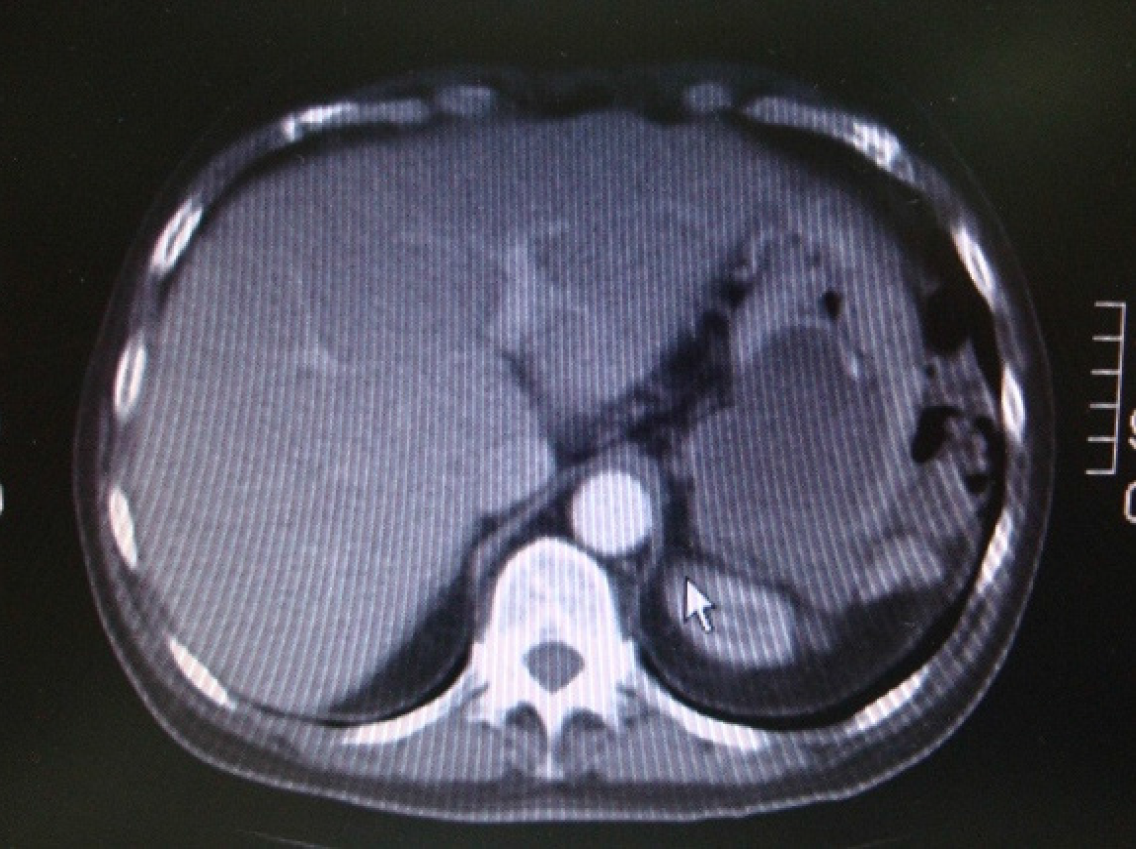

Figure 17 Enhanced computed tomography scan of the abdomen showing exterior compression of the stomach.